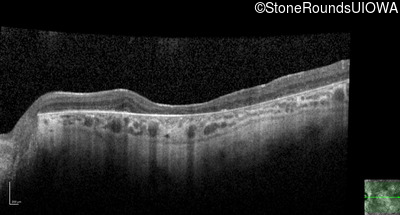

Age at visit: 38 years

This 38 year old woman had normal vision until age 22 when she noticed poor night vision when working as a camp counselor after college. Her hearing loss was first noticed at age 3 and was correctable with hearing aids.